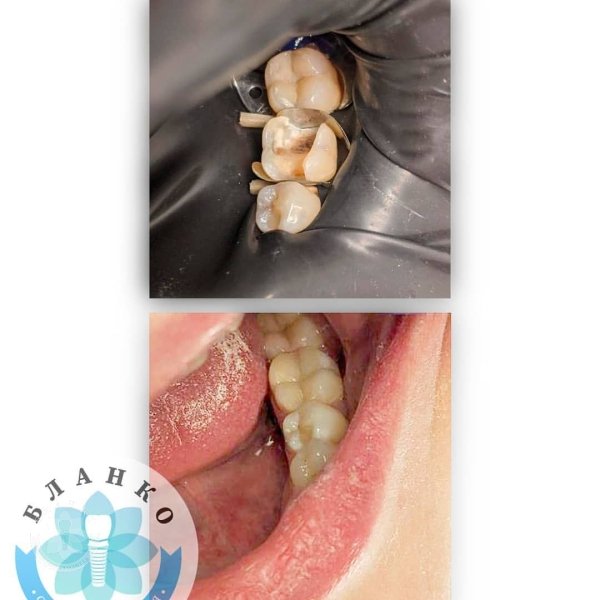

Глибока руйнація😳👿

Чим глибше під ясна зруйнований зуб — тим складніше він піддається адекватному відновленню☝

У даному клінічному випадку два зуби відновлено культевими вкладками, виготовлено коронки з оксиду цирконію, третій зуб відновлено за допомогою прямої фотополімерної реставрації 😁👍